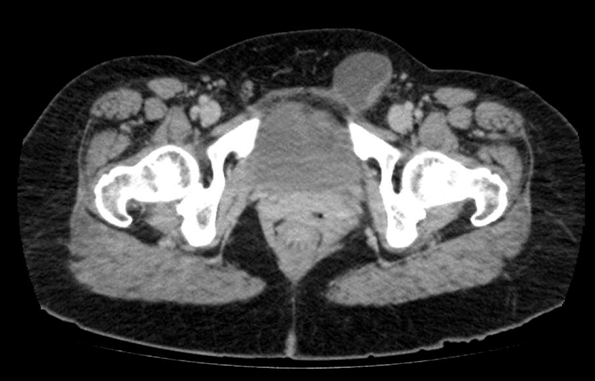

A computed tomography scan of the abdomen and pelvis showed a 4.3x3.2 cm ovoid structure arising from the peritoneal cavity, associated with the round ligament of the uterus and extending to the left labia majora (Figure 1). Hematological investigations were essentially unremarkable.

Figure 1: A computed tomography scan of the abdomen and pelvis showing a 4.2x3.2 cm ovoid structure arising from the peritoneal cavity and extending down to the labia majora representing a hydrocele of the canal of Nuck.